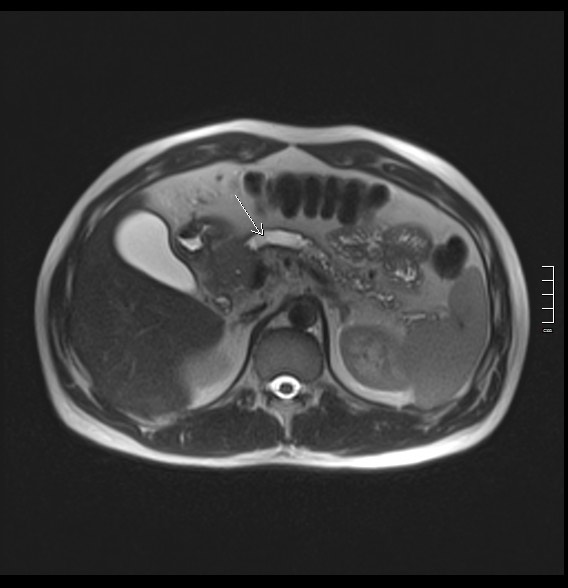

2912. Структура, указанная стрелкой, является